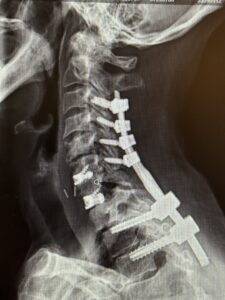

The patient is a 61-year-old female with a history of rheumatoid arthritis. She is 2-1/2-years status post C3-C7 laminectomy with posterior instrumentation and fusion. This procedure was performed to treat multilevel disc herniations with spinal cord compression following a motor vehicle accident.

She did well for several years, but then developed new onset of intractable neck pain with radiation to both upper extremities. She also had difficulty holding her head up.

Her rheumatologist ordered an x-ray which showed anterolisthesis of C7-T-1 with kyphosis and instability (Fig 1 right).